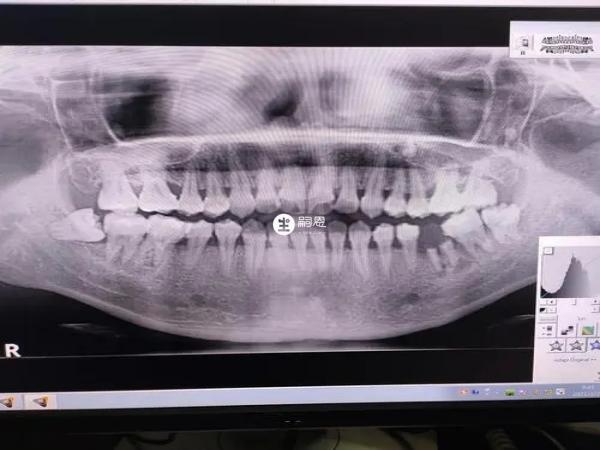

部分人后悔把烂牙根拔了主要还是因为费用昂贵,以及后期修复麻烦这两个因素影响。烂牙根如果没有完全龋坏是可以进行修复的,此时就不用强行拔牙根,但在修复前需要根据具体情况。如果牙根烂掉或者是局部牙根断裂,选择拔掉烂牙根后,单纯修补不能从根本上解决问题。牙根是支撑牙齿的物质,千万不能轻易拔除,除非是已经会影响到其他牙齿,否则都是不建议拔除的,在生活中可以通过X光片来判断牙齿的好坏情况,如果说牙根损坏的情况非常严重,此时留在口腔内已经没有任何作用了,医生就会建议拔除,此时拔除牙根是不会造成影响的,但是在拔牙之后可能会出现面部臃肿、口腔流血的情况,患者一定要做好消肿工作,同时也要防止口腔出现感染,导致牙龈再次受到伤害。

烂牙根是一种比较明显的口腔问题,这种情况下能否拔除需要根据医生根据口腔X光片,以及出现的口腔问题进项判定,牙根没有保留价值,医生会建议患者拔除烂牙根,部分人后悔把烂牙根拔了主要还是因为费用昂贵,以及后期修复麻烦这两个因素影响。